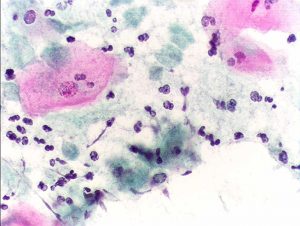

Trichomoniasis is caused by a microscopic parasite called Trichomonas vaginalis. It passes from person to person during sexual intercourse. The incubation period between exposure and infection is about 5 to 28 days.

To test for trichomoniasis, a doctor will use a microscope to look for the parasite in a sample. For women, the sample source is vaginal discharge. For men, the sample source is urine.

A doctor may then run further tests on the sample to confirm the presence of the parasite. These include a culture test, nucleic acid amplification test, or rapid antigen test.